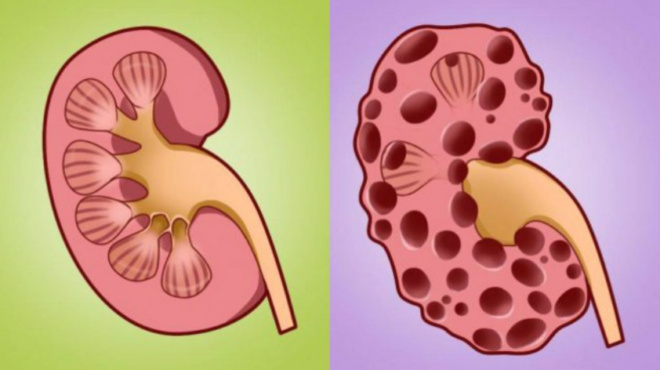

Πέτρες στους νεφρούς: Πρόκειται για μικρές και σκληρές αποθέσεις. Αυτές σχηματίζονται στους νεφρούς, με τη μείωση των ούρων. Μπορεί να σχηματιστούν και με την αύξηση κάποιων ουσιών. Όμως, ορισμένες τροφές βοηθούν στην αποτροπή του σχηματισμού των λίθων. Από εκεί και πέρα, μια πέτρα στο νεφρό είναι ένας σχηματισμός από μέταλλα. Αυτός μπορεί να έχει προκληθεί από μια σειρά διαφόρων αιτιών.

Πέτρες στους νεφρούς – Συμβουλές για την υγεία: Κοινά είδη

– Πέτρες οξαλικού ασβεστίου

– Πέτρες φωσφορικού ασβεστίου

– Στρώσεις από ρητίνη

– Πέτρες ουρικού οξέος

– Πέτρες από κυστίνη